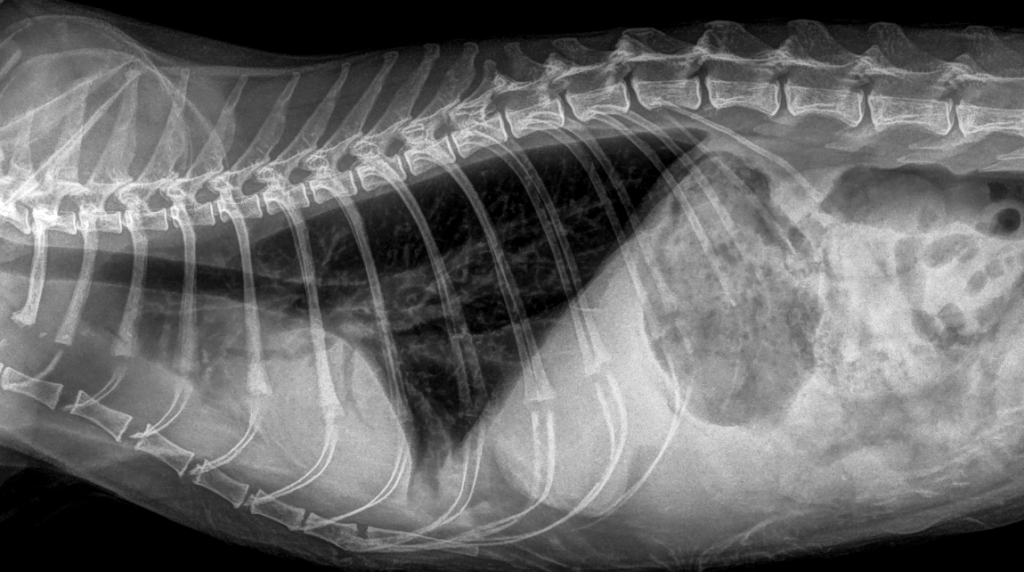

При биохимическом анализе сыворотки крови выявлено незначительное повышение уровней креатинина и мочевины, что согласуется с наличием в анамнезе хронической болезни почек у данного пациента (табл. 1). Клинический анализ крови демонстрирует выраженные изменения в составе эритроцитов (красных кровяных телец), что может свидетельствовать о развитии у пациента регенераторной анемии (табл.2), поскольку количество ретикулоцитов у него находится в пределах нормы (табл. 3). В свою очередь анемия как паранеопластический синдром отмечается у 43–58% кошек с лимфомой и у 30–43% собак. Она является неблагоприятным прогностическим фактором для обоих видов животных32-34.Рентгенография. После проведения рентгенографии грудной клетки в вентродорсальной и латеролатеральной проекциях выявлены следующие изменения: затемнение в области краниальных долей легких, сглаженность тени сердца. На рентгенограммах также обнаружены затемнения в каудальных долях легких, соответствующие ателектазу и смещению вентральной границы между вентральной стенкой грудной клетки, что может указывать на развитие гидроторакса в умеренном количестве (рис. 1, 2)